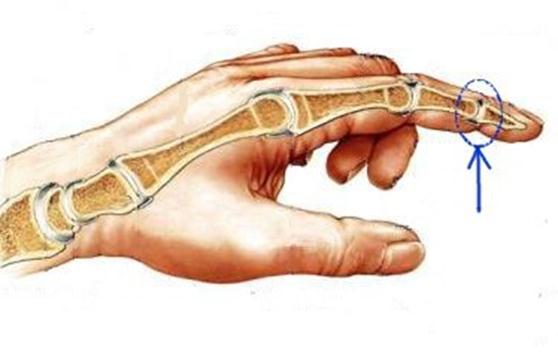

S: Стрелка указывает на art....

S: Стрелка указывает на art....

S: Стрелка указывает на art....

S: Стрелка указывает на art....